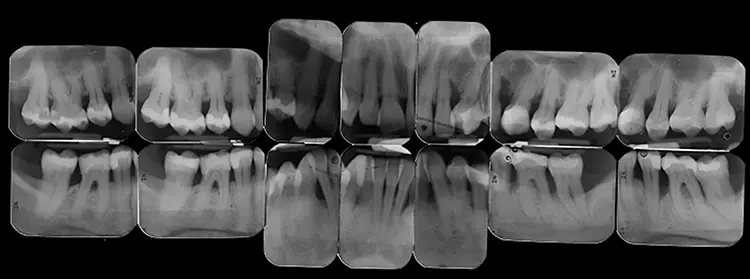

Der extraorale Befund war unauffällig. Der intraorale Befund (Abb. 2) zeigte eine lückenlose Dentition und eine verbesserungsbedürftige Mundhygiene (PI: 37%, BI: 2%) auf. Die Zähne 14 und 23 fehlten aufgrund einer Nichtanlage.

Einige Zähne waren konservierend suffizient versorgt (Abb. 3). In der Unterkieferfront bestand ein ausgeprägter Engstand mit Verschachtelung (Crowding).

Im Seitenzahnbereich bestanden an zahlreichen Zähnen Furkationsbeteiligungen. Die Zahnbeweglichkeit war an 2 Zähnen deutlich erhöht. An mehreren Zähnen lagen zudem gingivale Rezessionen vor.

- Generalisierter horizontaler Knochenabbau

- Lokalisierte vertikale Knochendefekte bei den Zähnen 22, 35, 32 und 42

- Radioluzenz im Furkationsbereich der Zähne 36, 46